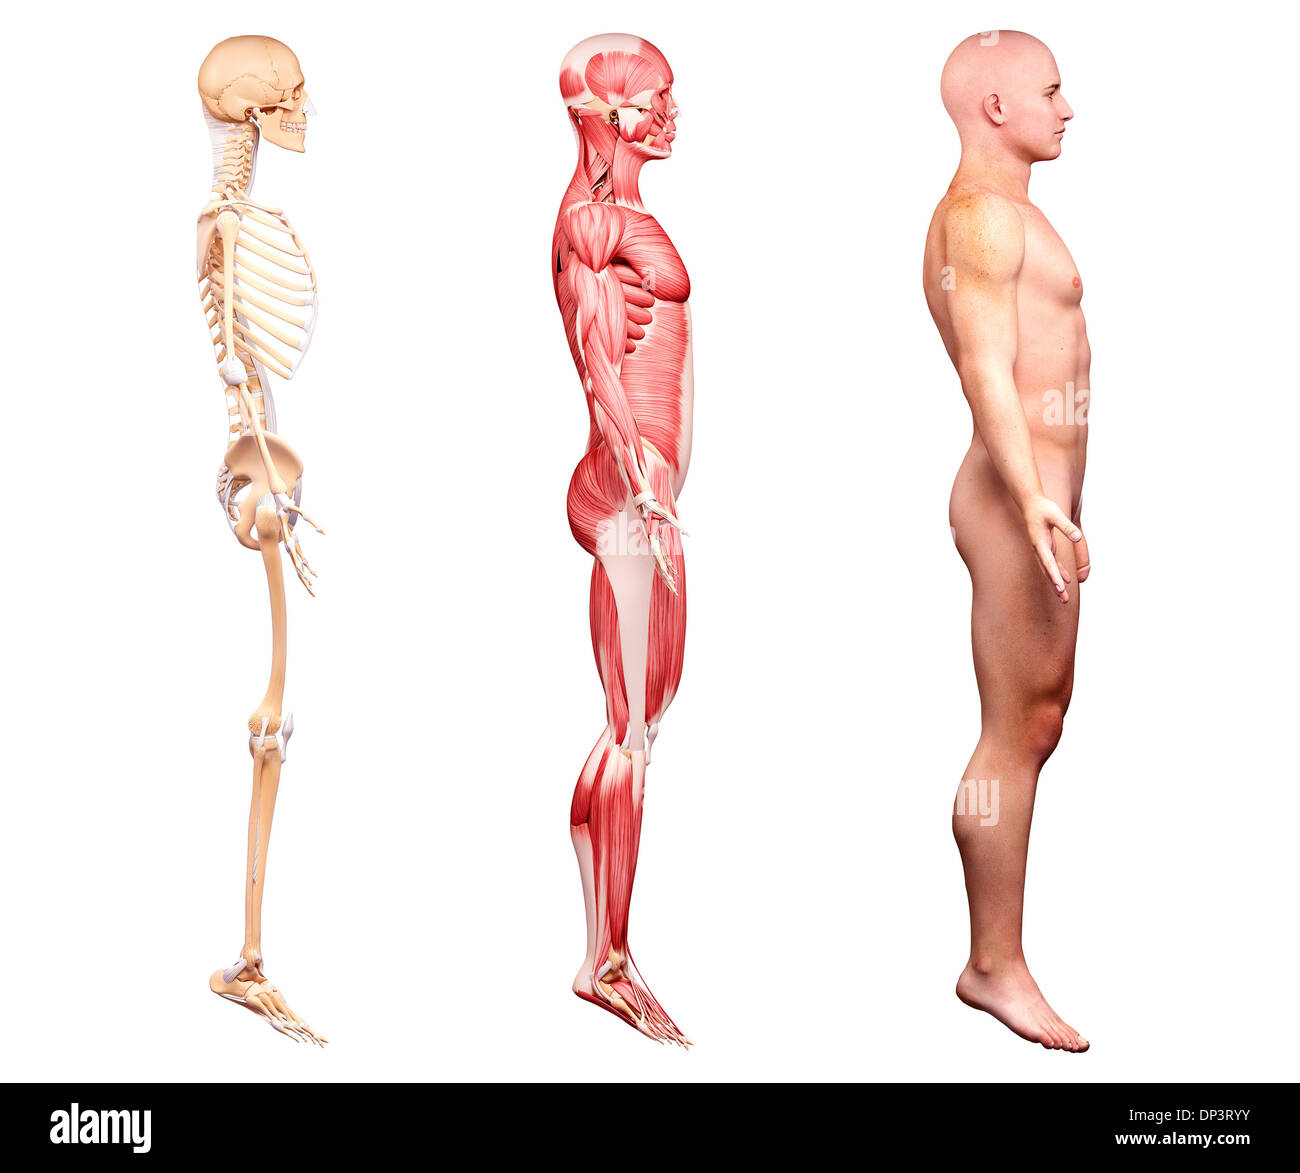

RMFX60TP–Menschen, Anatomie, Muskel, Körper, medizinische, Medizin, Illustration, Mann, Männlich, Gesundheit, muskulös, Wissenschaft, System, Biologie, Muskeln, ich

RF2A9AXYJ–Menschliche Körper Anatomie Muskeln Aufbau eines männlichen, Vorderansicht Seitenansicht und Perspektive, 3D-Rendering im Hintergrund